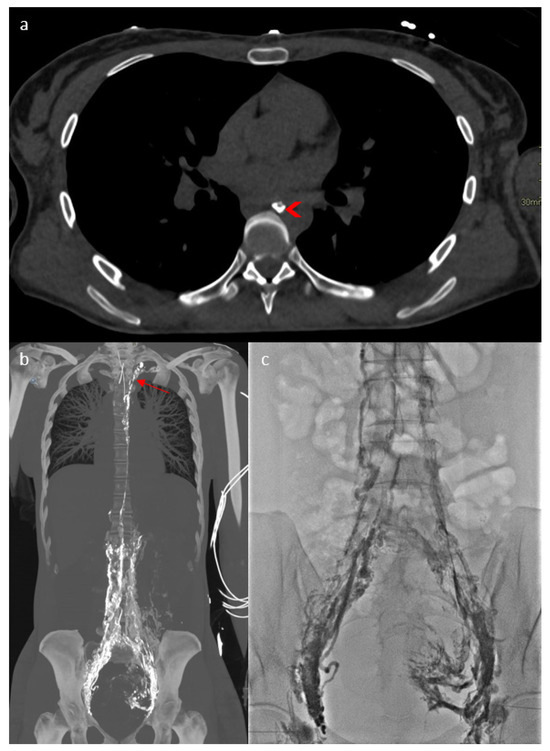

2. Case Report

3.2.3. Imaging